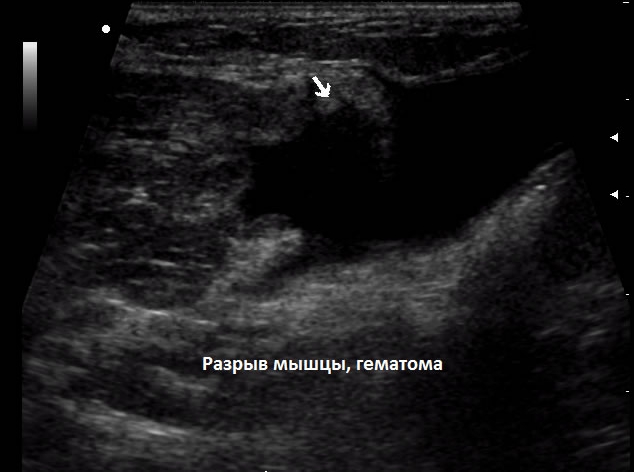

Частичные разрывы и микротравмы затрагивают двуглавую и приводящую мышцы. В таких случаях нарушение целостности может происходить на различных участках, включая место крепления к лонной кости. Растяжение связок бедра и мышечных тканей выявляется с помощью ультразвукового исследования. Для исключения перелома пациента направляют на рентгенографию. Если требуется более детальная оценка повреждений, может быть назначена компьютерная томография.

Если образовалась гематома, может потребоваться пункция для удаления жидкости. Лекарственные средства могут вводиться под кожу в области повреждения мягких тканей. При наличии кровотечения выполняется коагуляция поврежденного сосуда.